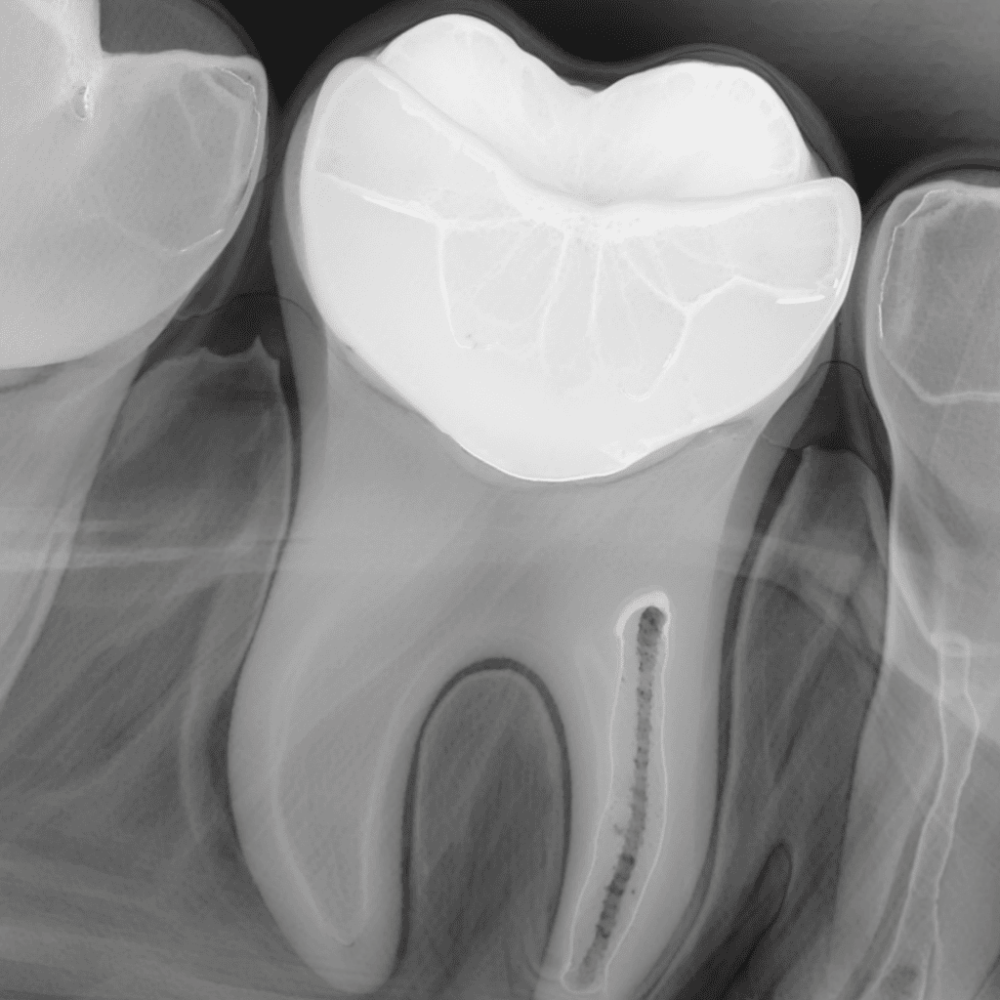

Прицельный снимок зуба или прицельная внутриротовая контактная рентгенография — это самый простой и быстрый способ узнать, что происходит внутри. С его помощью врач видит не только сам зуб, но и его корни, а также ткани вокруг.Такой снимок делают, чтобы найти скрытый кариес, заметить воспаление или кисту и проверить, насколько хорошо запломбированы каналы. Мы используем современный цифровой аппарат (визиограф), поэтому облучение здесь минимальное — это абсолютно безопасно. Звоните нам для консультации! (OOO «АС ДЕНТАЛ КЛИНИК». Лицензия № ЛО41-01197-26/01401624 выдана Министерством здравоохранения Ставропольского края 26.09.2024г. ИМЕЮТСЯ ПРОТИВОПОКАЗАНИЯ. НЕОБХОДИМА КОНСУЛЬТАЦИЯ СПЕЦИАЛИСТА.)

Стоимость: 300 рублей